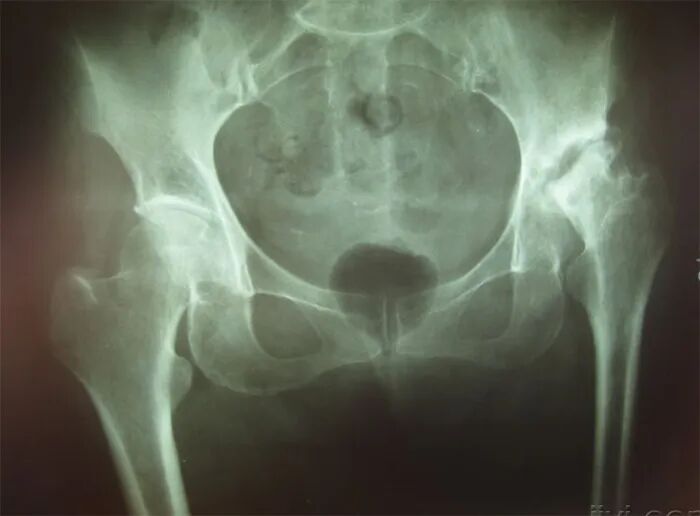

1、股骨头缺血性坏死

股骨头缺血性坏死是由于股骨头供血受损或中断,导致骨细胞和骨髓成分死亡,从而股骨头塌陷、相应部位疼痛及功能障碍。

疼痛:大腿内侧、臀部后侧和膝盖内侧或腹股沟区,活动后钝痛、针刺样疼痛加重。

关节僵硬导致活动受限:髋关节屈伸不利,不能长时间站立、下蹲困难和鸭步。

跛行:多为间歇性跛行。

活动受限:外展、外旋或内旋活动受限,患肢会缩短,肌肉萎缩。

保守治疗:一旦确诊,尽量避免负重,尽量卧床或拄拐,这样可以减缓股骨头坏死的进程,减少塌陷的机会。

手术治疗:建议尽快手术。早中期及时的手术干预可以防止股骨头塌陷,从而保留髋关节,一旦发展到晚期,只能通过髋关节置换手术恢复功能。